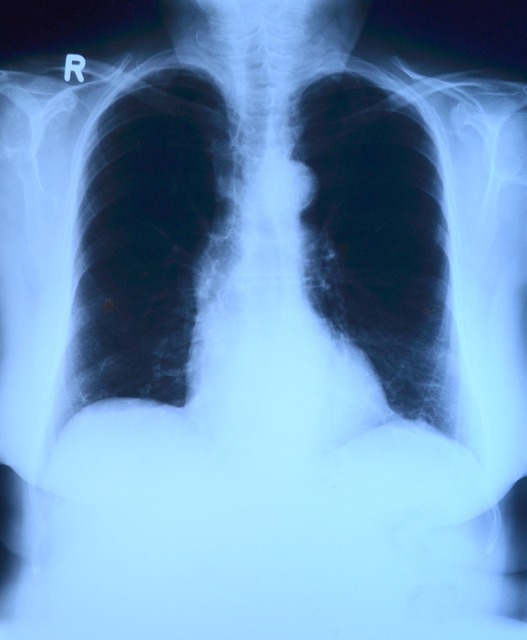

| 흉부 X-ray | 폐질환, 폐암 등 확인 | 매년 |